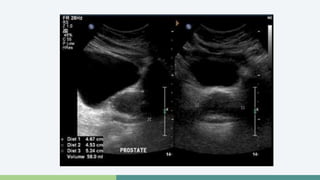

Ultrasonografía • TRUSse realiza después de un DRE anormal o PSA elevado • Biopsias • Lesiones hipoecoicas (60-70%) • Lesiones hiperecoicas (30-40%)

• TRUS se realiza después de un DRE anormal o PSA elevado

• Biopsias

• Lesiones hipoecoicas (60-70%)

• Lesiones hiperecoicas (30-40%)